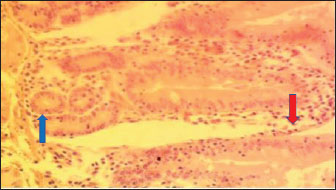

The histology of the duodenum in rabbits fed with diet 4 (SNLM) is displayed in Figure 4. The histological slide shows that the duodenum in rabbits consuming Synedrella nodiflora presents moderate necrosis of Lieberkühn crypts and mucosal epithelial cells, with inflammatory cell infiltration.

The histology of the duodenum in rabbits fed with diet 5 (LMM) is illustrated in Fig. 5. The histological slide shows that the duodenum in rabbits consuming a leaf meal mixture presents moderate necrosis of Lieberkühn crypts and mucosal epithelial cells, with mild infiltration of inflammatory cells.

Fig. 4. (SNLM): Section of the intestine showing moderated necrosis of Crept of Lieberkühn (blue arrow) and mucosal (arrow head) epithelial cells, with infiltration of inflammatory cells (red arrow) (x400; H & E).

Fig. 5. (LMM) Section of the intestine showing moderated necrosis of Crept of Lieberkühn (blue arrow) and mucosal (arrow head) epithelial cells, with mild infiltration of inflammatory cells (red arrow) (x400; H & E).

In the NLM shown in Figure 1, the mucosal lining was complete, with the Lieberkühn villi and crypts properly arranged. The epithelial layer, largely composed of absorptive enterocytes and goblet cells, was well preserved and did not show cellular erosion or necrosis (An et al., 2022). The lamina propria appeared to be free of inflammatory infiltrations, and the make-up was not atrophied or distorted, indicating a healthy mucosal barrier and optimum operational capacity (France and Turner, 2017). The TDLM (Fig. 2) had effects that showed cellular disintegration of the Lieberkühn crypts, signifying epithelial rejuvenation (Liu et al., 2019). At the same time, mucosal epithelial inner layer necrosis, shown by disturbed cellular structure and cytoplasmic degradation, suggests a distorted mucosal barrier that may amplify absorptivity, poor nutrient assimilation, and increased susceptibility to enteric pathogens (Chistiakov et al., 2014; De Medina et al., 2014). These observed changes can be due to the secondary metabolites like saponins, alkaloids, phenolics, and tannins present in Tithonia diversifolia, which are known to cause cytotoxic, anti-proliferative, and membrane-disrupting activities in the GIT tract when taken unprocessed (Abdelsalam and Fathi, 2023). These observations demonstrate the need for detoxification, quantification, and probably fermentation when incorporating TDLM into the diet of local rabbits (Abd-Elghany et al., 2021). Although TDLM provides a good source of nutritious and phytogenic benefits, its raw inclusion must be controlled to avoid compromising gut integrity and performance (Sugiharto et al, no date). In the observed PBLM in Figure 3, the necrosis in the crypt of Lieberkühn shows disturbance of the proliferative region crucial for epithelial regeneration and intestinal homeostasis (Chistiakov et al., 2014). Impairment of the crypts affects enterocyte production, which may cause weakened absorptive and digestive effectiveness in the small intestine (Buckley and Turner, 2018). Concurrently, mucosal epithelial cell degeneration and necrosis show intestinal barrier failure, increasing the danger of luminal antigen translocation and mucosal susceptibility (An et al., 2022). The permeation of inflammatory cells, mainly lymphocytes and macrophages, demonstrates a limited immune response that may be a reaction to epithelial injury caused by phytochemicals in Parkia biglobosa leaves (Franz et al., 2019). These bioactive constituents possess antioxidant and antimicrobial properties and may cause cytotoxic effects at high levels of inclusion in unprocessed form. Tannins and saponins can tamper with membrane integrity, modify gut microflora, and trigger mucosal irritation (De Medina et al., 2014). These effects are consistent with the inflammatory and degenerative changes observed in the duodenal mucosa (Chistiakov et al., 2014; De Medina et al., 2014). The observed necrosis in the crypt that controls epithelial cell production and mucosal renewal in rabbits fed SNLM indicates weakened cellular turnover (Buckley and Turner, 2018). Moreover, the loss of mucosal epithelial cells’ integrity shows that the absorptive and protective barrier is compromised, which is crucial for nutrient uptake and host protection (Liu et al., 2022). The infiltration of inflammatory cells, principally comprising lymphocytes and plasma cells, into the lamina propria, as shown in Figure 4, demonstrates an ongoing immune response that may have been prompted by mucosal or antigenic disturbance from biologically active compounds in Synedrella nodiflora. If the concentration is not regulated, this can lead to a cytotoxic or pro-inflammatory effect on the mucosa of the GIT (Jha et al., 2019). Specifically, saponins are known to disrupt membranes and increase gut penetrability, possibly leading to reactionary inflammation and epithelial damage (Ohimain et al., 2020). Necrosis of the Lieberkühn crypt observed in the LMM (Fig. 5) and damage to the mucosal epithelial cells affect the intestinal epithelium, compromising absorptive and secretory activities crucial for gut health (Buckley and Turner, 2018). This pattern is consistent with that observed in other leaf meals; however, the infiltration of inflammatory cells appeared mild, suggesting a moderate but continuous controlled immune response, possibly to clear away cellular fragments and restore mucosal integrity (Chistiakov et al., 2014; De Medina et al., 2014). This trend aligns with subacute intestinal damage, where soreness is present but not distressing, enabling mucosal recovery if the injurious stimuli are removed (France and Turner, 2017; An et al., 2022).